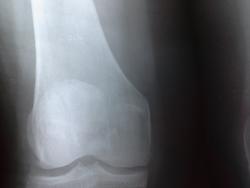

В проекции н/3 диафиза по задней поверхности-это артефакт. А по задней поверхности  на уровне суставной щели-мягкие ткани, симметрично с обеих сторон, разве нет?

20131205_085903.jpg20131203_131021-1.jpg

Насчёт артефакта - Вам как автору ветки виднее (оригинал у Вас в руках), нам - отсвечивает только тот артефакт. А изображения анонимизируйте. Информацию о пациентах и мы как врачи умеем хранить.)

Да, косяк мой, увлеклась...согласна, исправлюсь...А с заключением-то мысли какие-нибудь есть помимо артефактов и теней по задней поверхности ...???

К великому сожалению пациентка на сегодняшний день к нам не явилась...Ждемс...я выставила дифряд: костный инфаркт,энхондрома, хондросаркома и рекомендовала ей КТ.